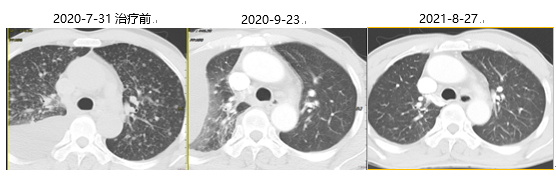

2020年7月31日

胸部CT:上叶纵隔旁见结节灶,大小2.9cm×2.2cm×2.9cm,双肺弥漫多发粟粒结节灶,大小不等。纵隔内(2R、4R、4L区)多发肿大淋巴结,较大者短径约1.0cm。右侧胸腔积液。

图片YkT帝国网站管理系统

胸部CT提示:口服阿美替尼2个月后,原双肺弥漫粟粒结节灶已明显减少、缩小;纵隔淋巴结转移较之前好转;双肺多发转移较前好转。8月26日末次随访时右肺上叶纵隔旁见少许不规则软组织密度结节影,双肺磨玻璃结节直径不足0.5cm,纵隔及肺门未见肿大淋巴结。YkT帝国网站管理系统